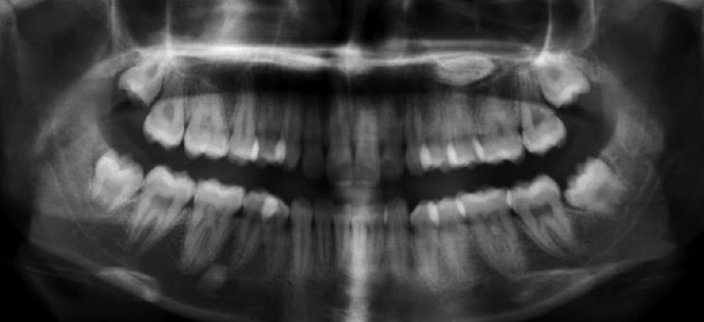

1.Lower adult CI there? YES. so def 6-7

1. Upper adult CI there (they normally erupt 7-8)? NO, baby ones should shed at 6-7.

Conc: pt. Is 6 y.o